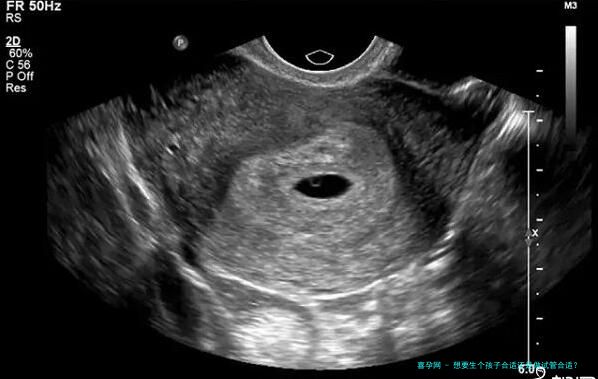

是一种相对简单且本钱较低的辅助生育技术。它主要适用于那些因男方轻度精子问题或双方同房障碍而难以自然受精的夫妇。在这方面期间医生会在合适的时间将处理过的精子注入女性体内,以期达到受孕的目的。

相比于,试管婴儿技术则看起来更以高为科技且精细化。它适用于许多种繁杂的受孕障碍,如严重的输卵管问题、精子质量问题,甚至是不明缘由的不孕症。